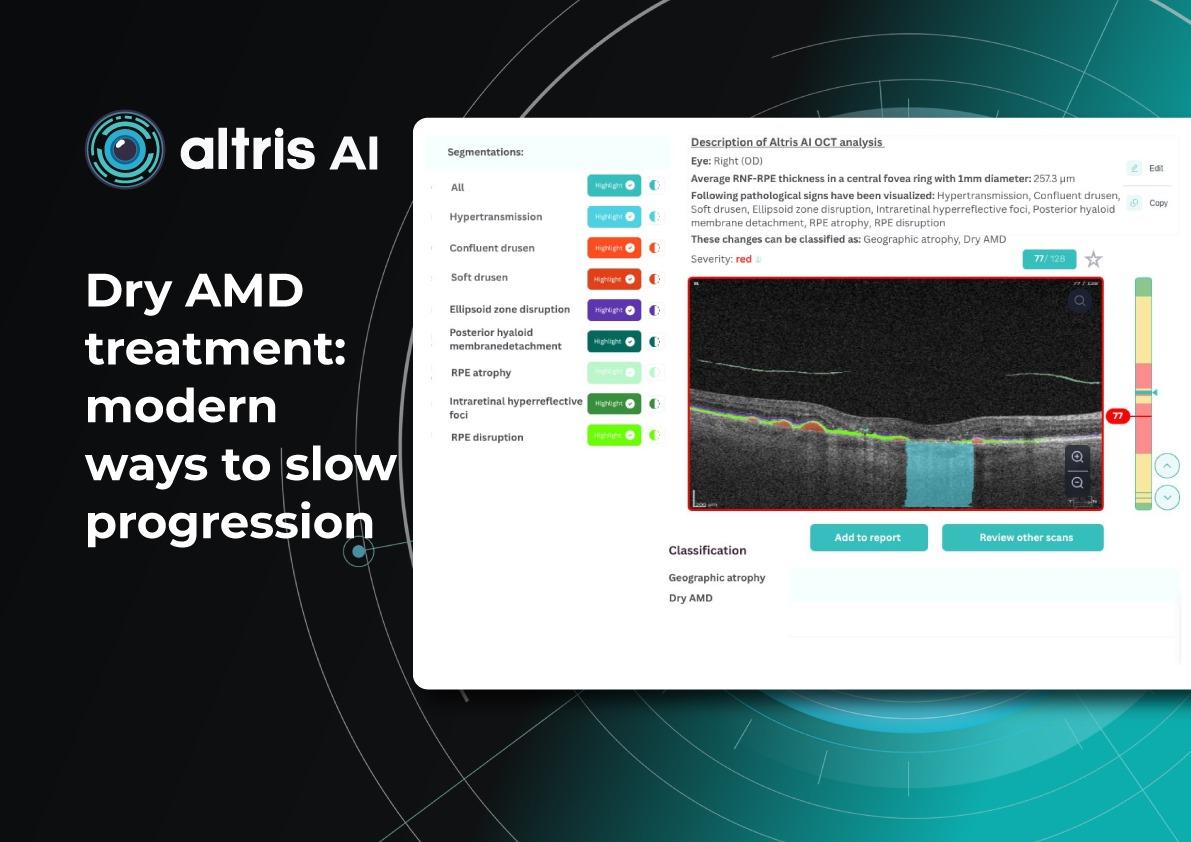

Dr. Maria Sampalis, OD, the owner of Sampalis Eye Care, Rhode Island, utilizes two such programs in her practice. To support her specialization in dry eye management, she employs CSI Dry Eye. Additionally, she uses Altris AI, an AI-powered platform for OCT scan analysis, to provide a second opinion and enhance diagnostic accuracy.

Dr. Sampalis finds that the Dry Eye software allows her and her staff to analyze symptoms and images comprehensively, improving patient care, time savings, and increasing diagnostic precision. See how OCT AI works here.

Her patients also appreciate Altris AI, which analyzes OCT scans for over 70 pathologies and biomarkers while also calculating the risk of developing glaucoma.

Eye Place, an optometry center in Columbia, also leverages Altris AI, among other cutting-edge technologies. They capture images using the Topcon Maestro2 OCT and use Image Net6 software to export DICOM files to the Altris AI platform.

To illustrate the point, here is a handwritten referral compared to one of the types of customised OCT report from the Altris AI system, a platform that automates AI-powered OCT scan analysis for 70+ pathologies and biomarkers. This screenshot, in particular, shows segmented retina layers and highlights biomarkers of Dry AMD alongside a comparison of the patient’s macular thickness over visits.